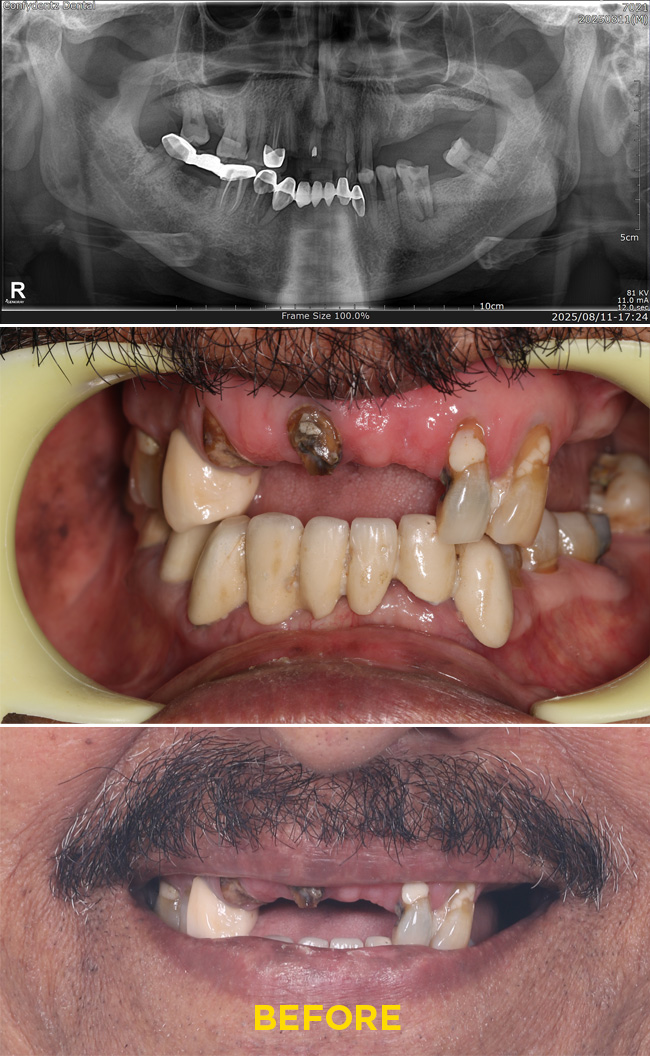

Case - 4